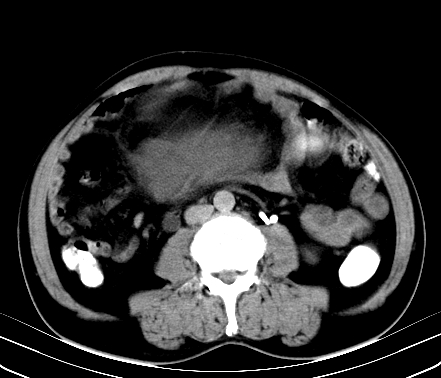

标题: CT19729B:男,74岁,因腿疼就诊,查体触腹部肿物, [打印本页]

标题: CT19729B:男,74岁,因腿疼就诊,查体触腹部肿物,

增强扫描

动脉期

【ct表现】

1、肿块巨大,往往位于腹膜后,长大后才引起症状而就诊;那么位于腹膜后的肿瘤80%为恶性肿瘤。

2、实性肿瘤,增强扫描轻度不均强化,实性肿瘤一般不是好东西。

3、肿瘤边缘似见少许脂肪样密度。

4、腹膜后未见肿大淋巴结,但肿瘤于临近的肠管及组织接触紧密。

【诊断】

腹部占位,考虑位于腹膜后的恶性肿瘤,脂肪肉瘤(实体型)可能性大。

术后病理结果:腹膜后脂肪肉瘤。